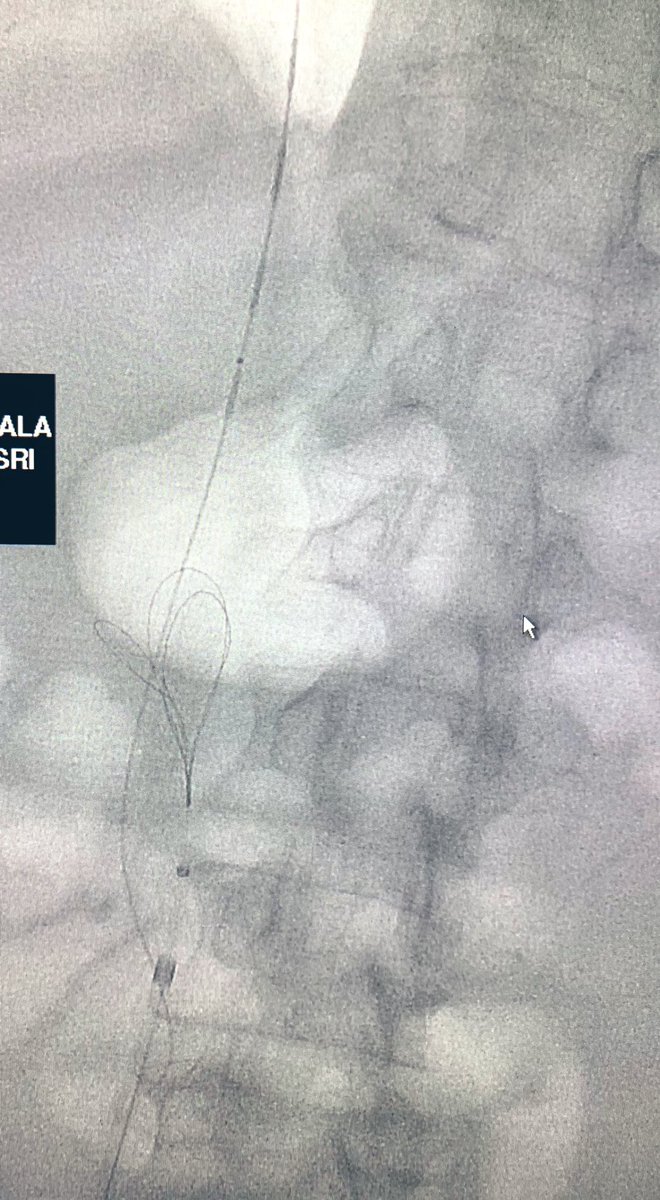

56 Y O known Chronic Liver Disease with Isolated Gastric Varices. Treated by

#Balloon#Occlusion Transvenous#Obliteration and#VascularPlug Placement#Intervention#Radiology#Makkahpic.twitter.com/0eup4cuY7x